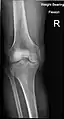

X-ray

Knee X-ray

Knee X-ray (weight bearing)

Knee X-ray (weight bearing, flexion)